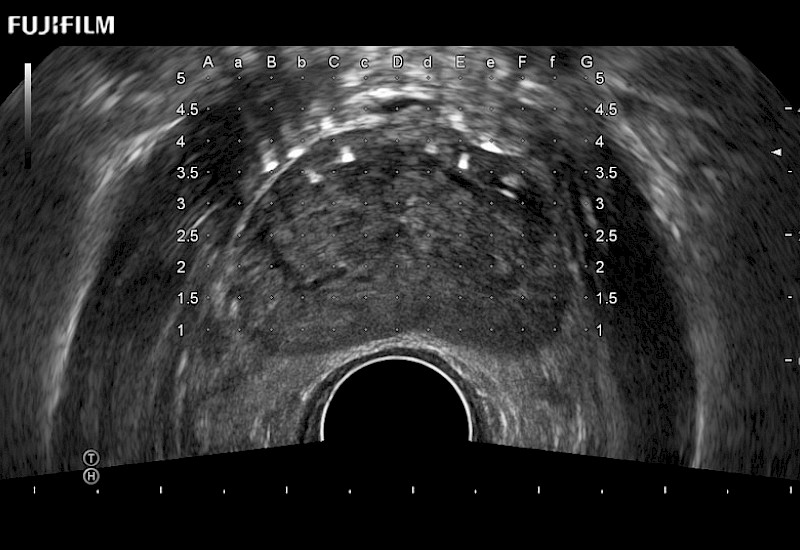

Exclusive 200° FOV end-fire prostate biopsy transducer.

Main Specifications:

Provides real-time imaging of both the sagittal and transverse planes